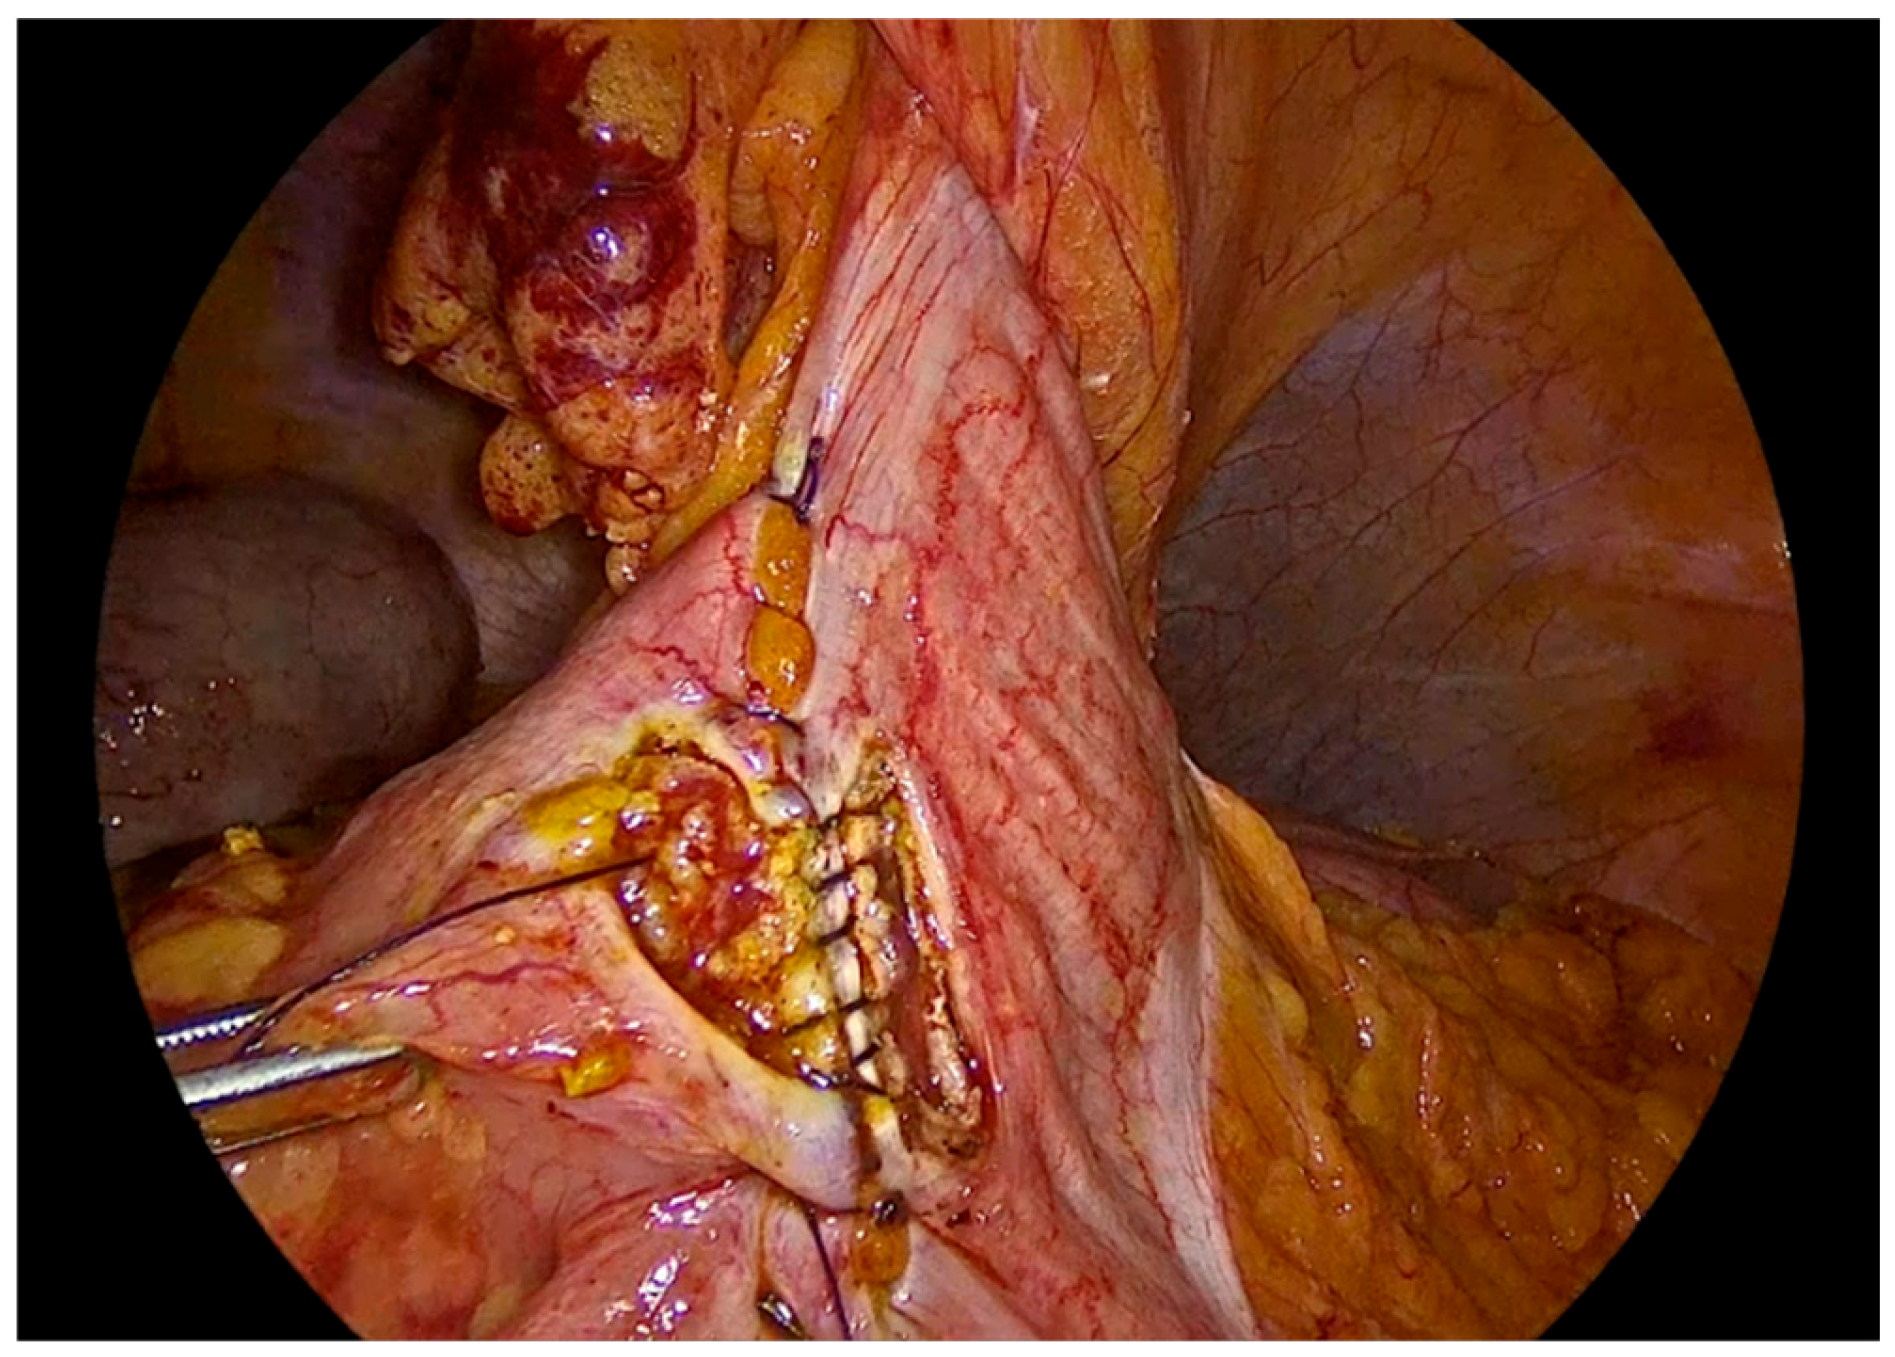

The anastomosis begins with a continuous seromuscular layer using a barbed 3-0 non - absorbable suture, extending for approximately 8 to 10 cm, providing reinforcement and support to the anastomosis.

Figure 6. Side to side isoperistaltic sutured alignment of transverse colon with ileum.

Enterotomies are subsequently created on the antimesenteric borders of both bowel segments, at approximately 1 cm from the outer suture line, with a length of 3 to 4 cm.

Figure 7. Enterotomies of bowel ends.

Preprints 195043 g007